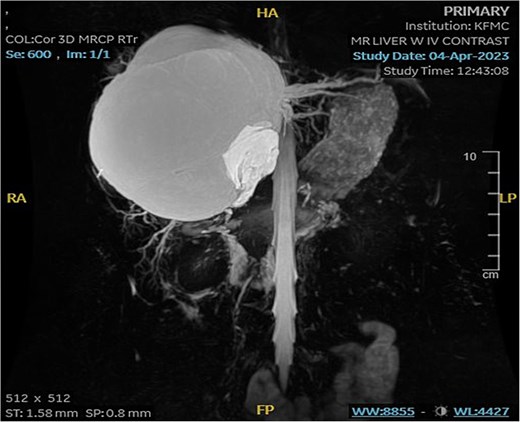

The mass had fine, minimally enhancing septations without any solid enhancing component. Communication with the right intrahepatic biliary ducts was observed, leading to moderate intrahepatic biliary duct dilatation. Magnetic resonance imaging (MRI) of the liver using contrast reveals a large hepatic cystic mass, corresponding to dimensions noted on CT, showing bright T2 signal intensity with thin septations without a solid component, illustrated in Fig. 2.

MRI of the liver: Demonstrating the mass in T2. Mild splenomegaly was noted without focal lesions. A) Transverse view, B) longitudinal view.

Mild splenomegaly (13.4 cm) with no focal lesions was noted, which exerted a mass effect on the patent hepatic vasculature. No osseous lesions or lymphadenopathies were identified. Three smaller bright T2 signal intensity lesions that did not enhance on post-contrast scanning were seen in segments 7 and 6, with measurements 0.2 × 0.1 cm, 0.7 × 0.7 cm, and 0.9 × 0.4 cm, respectively. The consistency of the cyst is evident from Fig. 3.

MRI of the liver: Demonstrating smaller bright T2 signal intensity lesions without post-contrast enhancement were observed in segment 7 and segment 6, consistent with cysts.